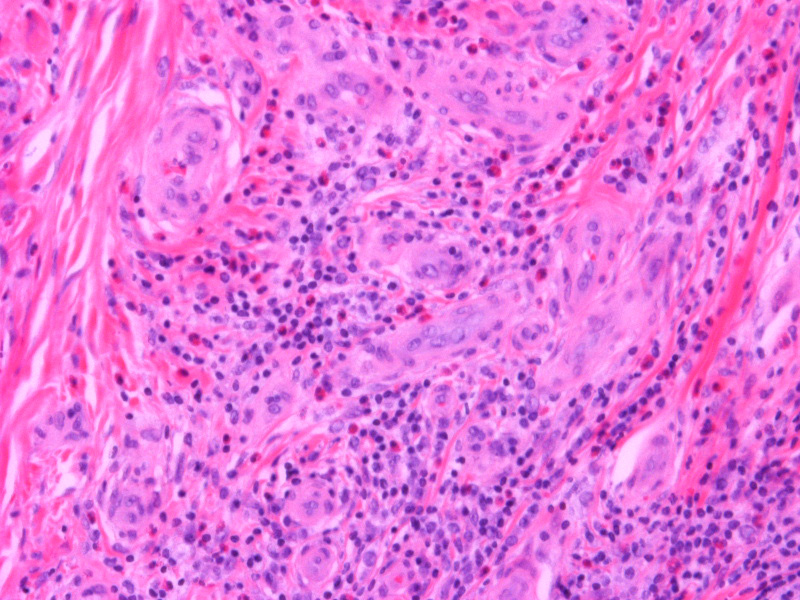

Atlas of skin histopathology

Angiolymphoid hyperplasia =فرط تنسج لمفواني وعائي0